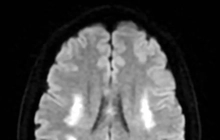

U não và các khối u tủy sống: Người trẻ tuổi có nhiều khả năng phát triển các khối u ở phần trên của bộ não. Khối u tủy sống ít phổ biến hơn. Các khối u não có thể gây đau đầu, buồn nôn, nôn, mờ mắt hoặc nhìn đôi, chóng mặt, co giật, đi bộ khó khăn,...

Có hai dạng u não: u não sơ cấp (bắt đầu từ những tế bào trong não) và u não thứ cấp (đến từ một dạng ung thư khởi phát từ một phần khác của cơ thể và lan tới não). Phần lớn u não thường gặp ở thanh thiếu niên là dạng sơ cấp. Hai trong số nhiều dạng phổ biến là astrocytomas (u não bắt nguồn từ những tế bào não tên là astrocyte, dạng này không di căn ra khỏi não và tủy sống, không ảnh hưởng các tổ chức khác) và ependymomas (bắt nguồn từ niêm mạc trong não thất).